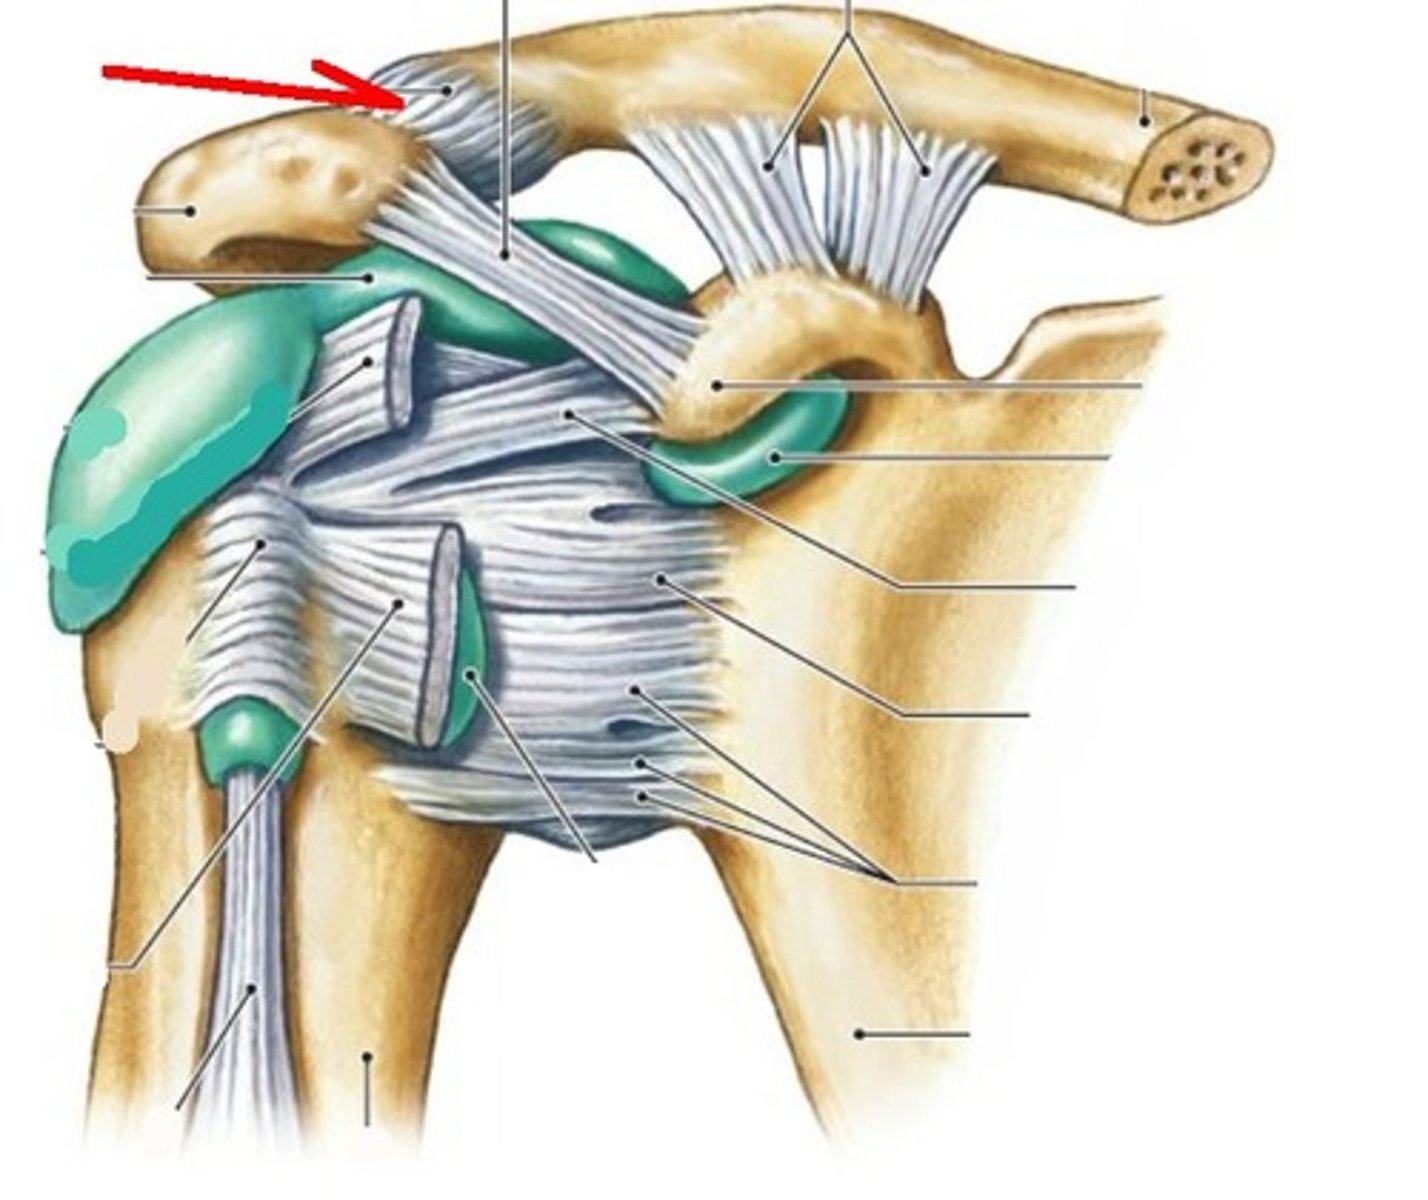

coracohumeral ligament

glenohumeral ligament

What is the shoulder joint reinforced by?

4 rotator cuff tendons

Inferior dislocation

Acromioclavicular ligament